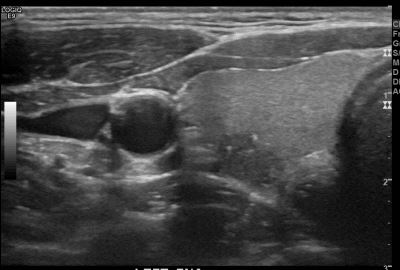

상기환자  외부 건진상 이상소견으로 내원하신 30대 중반 남성분으로 의심스러운 갑상선 좌엽 결절 세포검사진행후 갑상선암으로 진단되었습니다